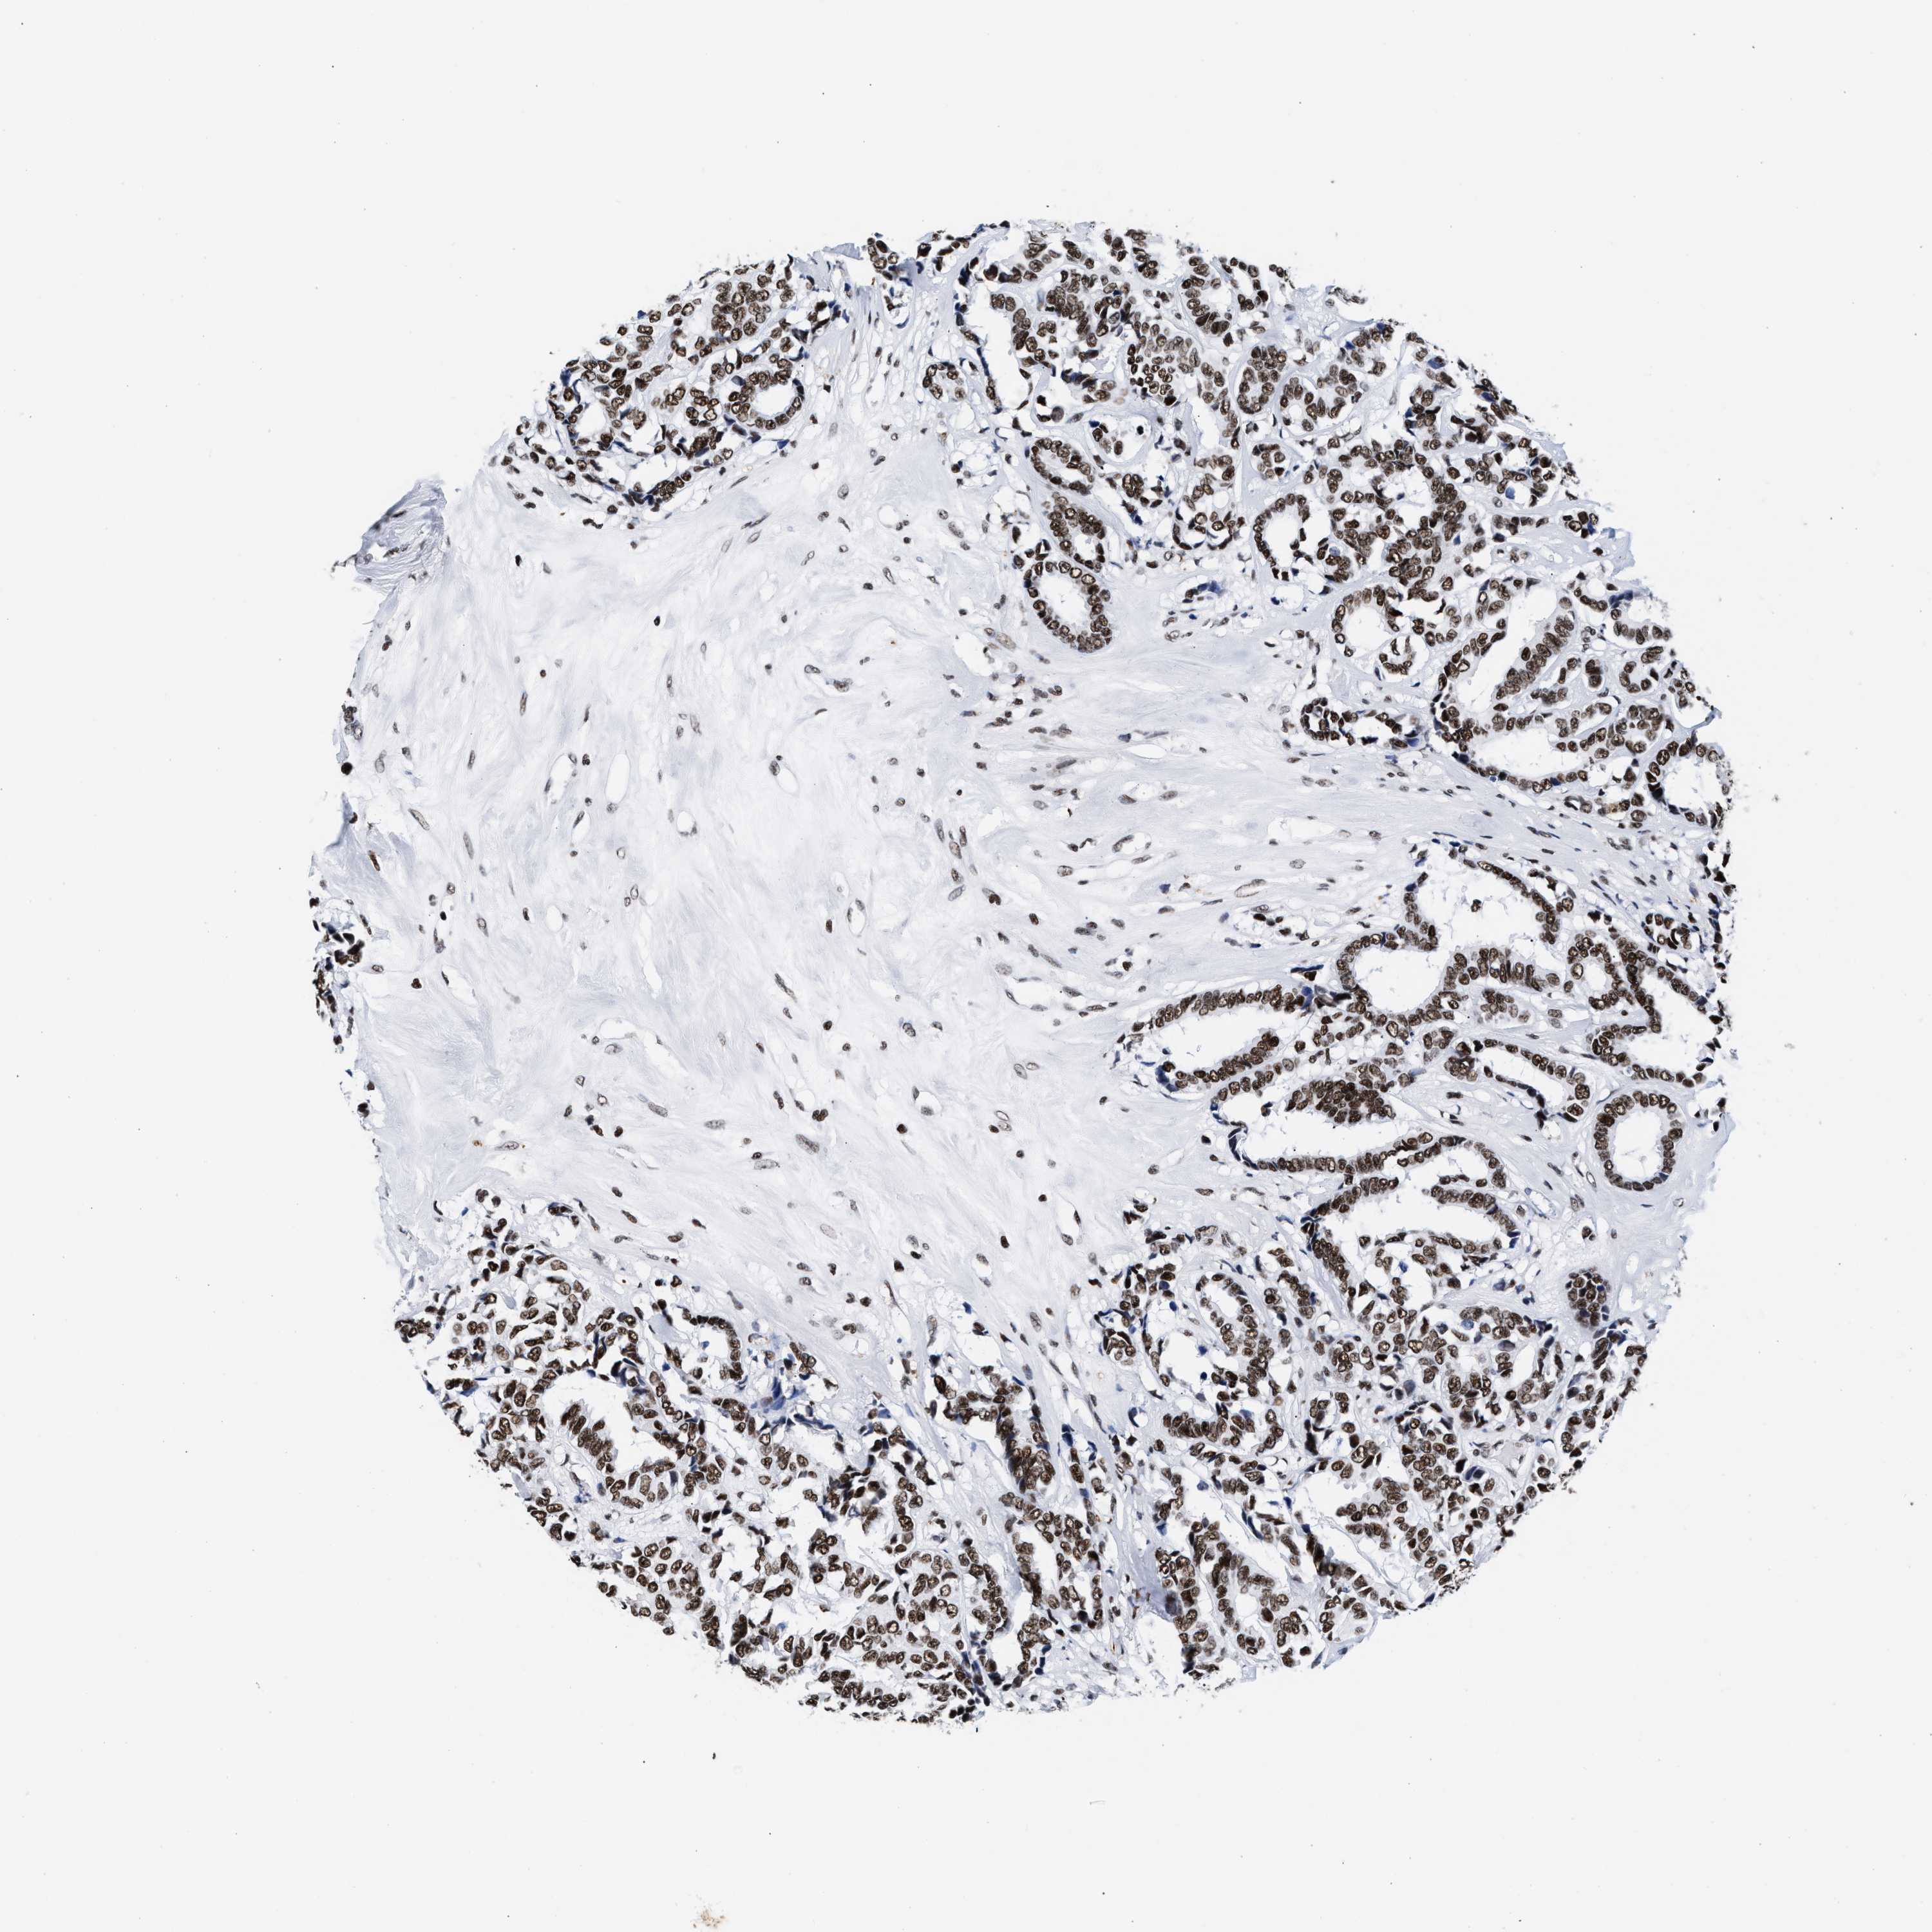

CANCER BREAST CANCER Show tissue menu

BRCA TCGA BRCA VALIDATION PROTEIN EXPRESSION